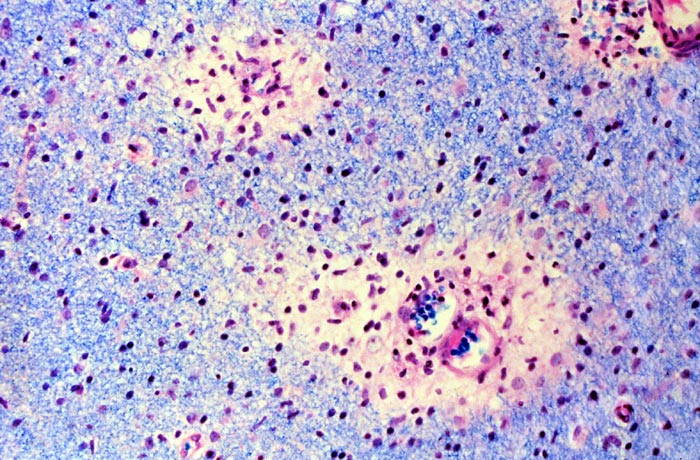

Информация о диссеминированном рассеянном энцефаломиелите